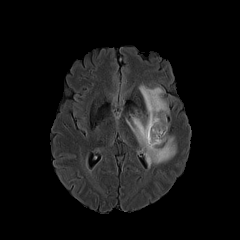

We introduce a neural network framework, utilizing adversarial learning to partition an image into two cuts, with one cut falling into a reference distribution provided by the user. This concept tackles the task of unsupervised anomaly segmentation, which has attracted increasing attention in recent years due to their broad applications in tasks with unlabelled data. This Adversarial-based Selective Cutting network (ASC-Net) bridges the two domains of cluster-based deep learning methods and adversarial-based anomaly/novelty detection algorithms. We evaluate this unsupervised learning model on BraTS brain tumor segmentation, LiTS liver lesion segmentation, and MS-SEG2015 segmentation tasks. Compared to existing methods like the AnoGAN family, our model demonstrates tremendous performance gains in unsupervised anomaly segmentation tasks. Although there is still room to further improve performance compared to supervised learning algorithms, the promising experimental results shed light on building an unsupervised learning algorithm using user-defined knowledge.